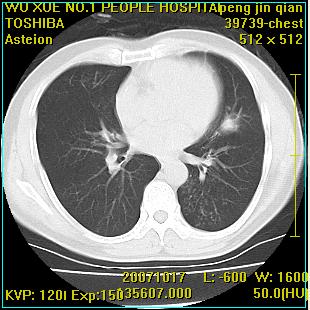

标题: CT10148:男,56岁,咳血。 [打印本页]

标题: CT10148:男,56岁,咳血。

左肺上叶尖段占位性病变,考虑肺癌.癌性空洞,并双肺转移灶及纵隔淋巴结转移

左肺上叶尖后段较大团块影,边缘光滑,内见不规则裂隙样空洞,周围明显见细小结节及渗出,与肺门方向结构紊乱,另:左上叶尖段外侧 舌叶内侧 右上叶尖段及下叶背段均见片状致密影。考虑:继发性肺结核伴空洞形成!

左上肺厚壁空洞影、两肺多发小片样不规则高密度灶。基本上能排除转移瘤。考虑肺结核伴空洞形成。

左上肺后壁空洞,内壁不规则,可见壁结节;左上叶尖段外侧 舌叶内侧 右上叶尖段及下叶背段均见片状致密影。考虑:左肺肺癌并两肺继发性肺结核?